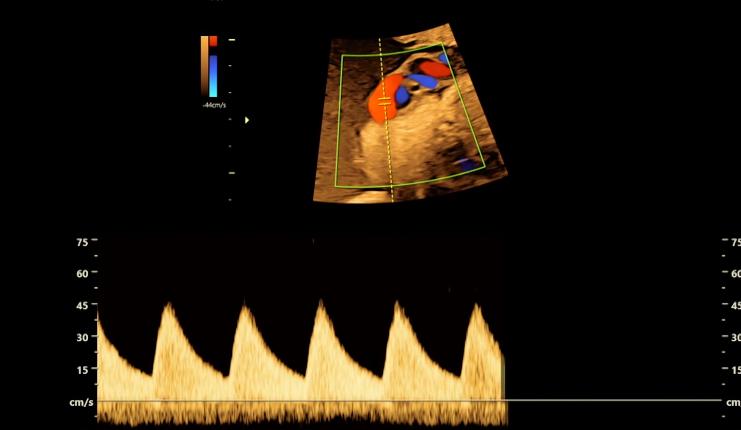

巴斯基医生决定采用间质内激光治疗,也就是把一根非常细的针从贝基的腹部穿刺进入胎儿的肺里,再把激光纤维插进细针中,通过发射高能的激光脉冲来堵住那根输送血液和营养物质的供血管

贝基的手术日很快到来,巴斯基医生评估这次手术的风险系数极高,手术是在胎儿的3.5-4厘米大的胸腔内进行,供血管的粗细不到一根火柴棍,而肿瘤却有拇指那么大,一旦手术进行中出现1、2毫米的误差,后果将不堪设想。

巴斯基医生只能依靠模糊的B超投影仪来寻找肿瘤的位置,尽管如此,他还是凭借丰富的经验将针管快狠准地扎进了准确位置,接着激光纤维的导入也很顺利,巴斯基医生没有丝毫犹豫,迅速找到了供血管的位置并利用激光堵住了它,不一会B超显示胎儿正在向胎盘泵血了,这就意味着手术结果的顺利和成功,巴斯基医生的沉稳操作甚至让肚子里的胎儿没有察觉到任何异常,听到这个天大的好消息,贝基和丈夫都喜极而泣,现在,她的女儿终于可以平安长大了。